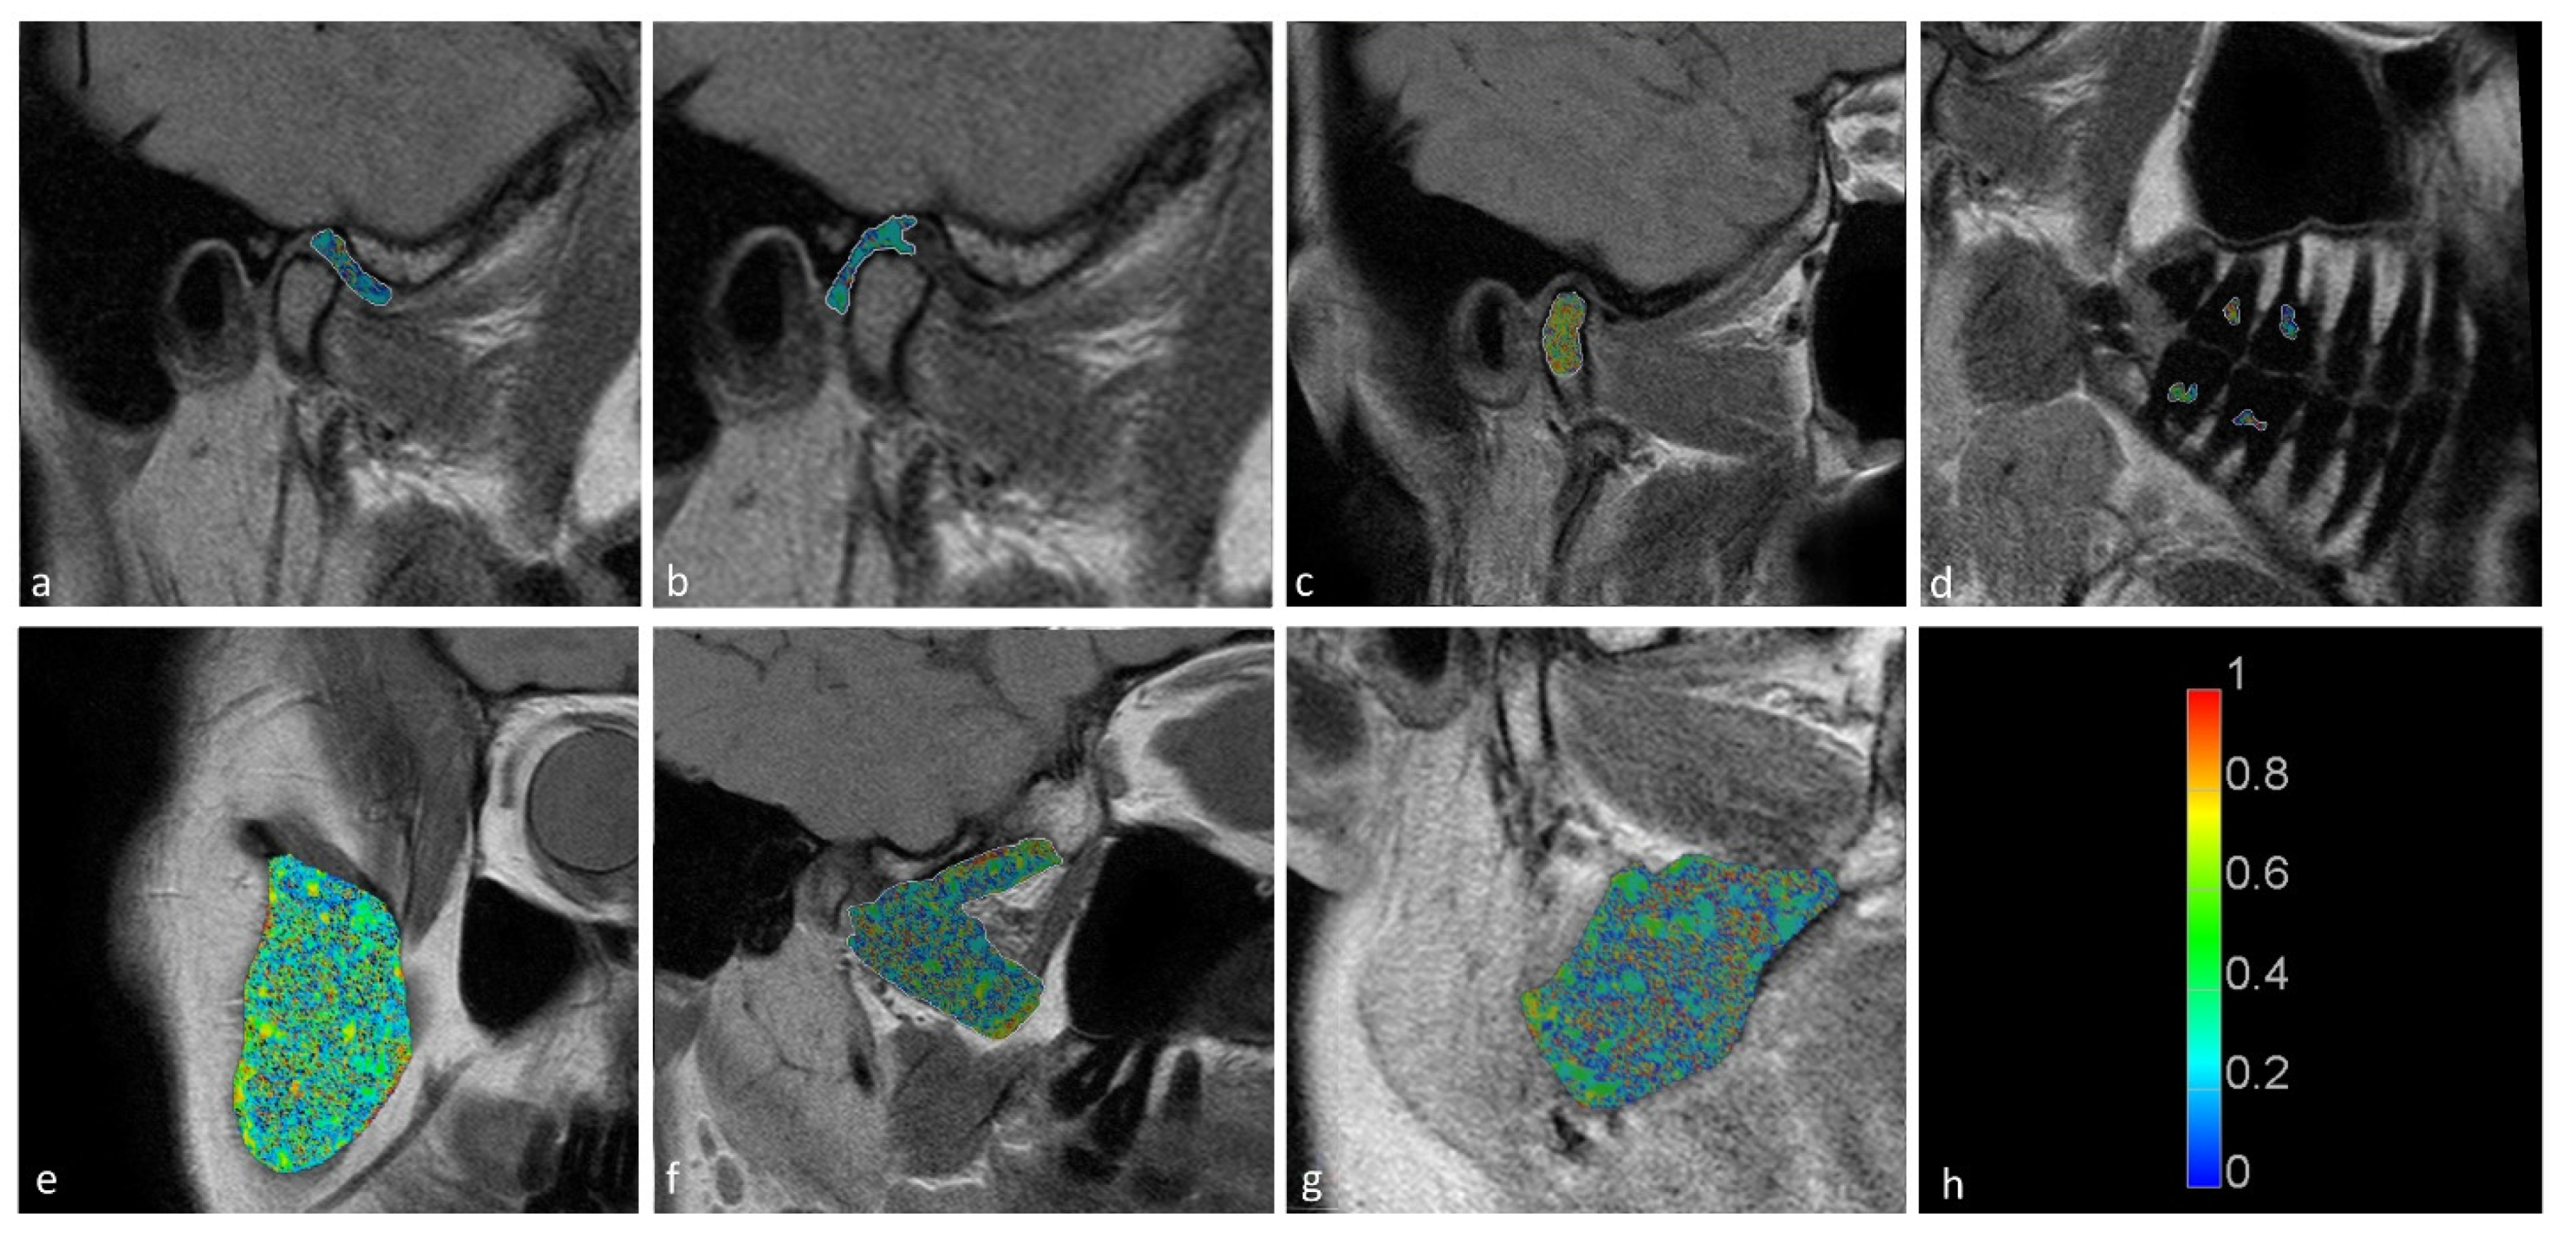

The temporomandibular disk, retrodiscal tissue, condylar bone marrow, masseter muscle, lateral pterygoid muscle medial pterygoid muscle, and dental pulp of the first and second molars were manually segmented by the dentist. The segmentation was performed twice at an interval of two months, with manual contour tracing using the VisNow Plugin Medical library [20] (Figure 1). Segmentation was performed on all slices containing the relevant structure. Due to missing molars, segmentation and further analysis of the pulp was not possible in eight joints. The intrarater reliability was assessed with the intersection-over-union measure. The average of two measurements was taken into consideration in further statistical analysis.

Figure 1. Samples of stomatognathic anatomical structure segmentation for the (a) disk; (b) retrodiscal tissue; (c) bone marrow of the condyloid process; (d) pulp; (e) m. masseter; (f) m. pterygoideus lateralis; and (g) m. pterygoideus medialis.